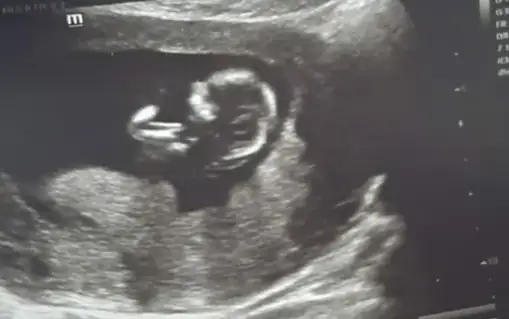

Merhaba 12+4 haftalık nub teorisi ile tahminde bulunabilir misiniz. Teşekkür ederim.

Eklentiler

• 20220221_100239.webp

20220221_100239.webp

14,2 KB · Görüntüleme: 88